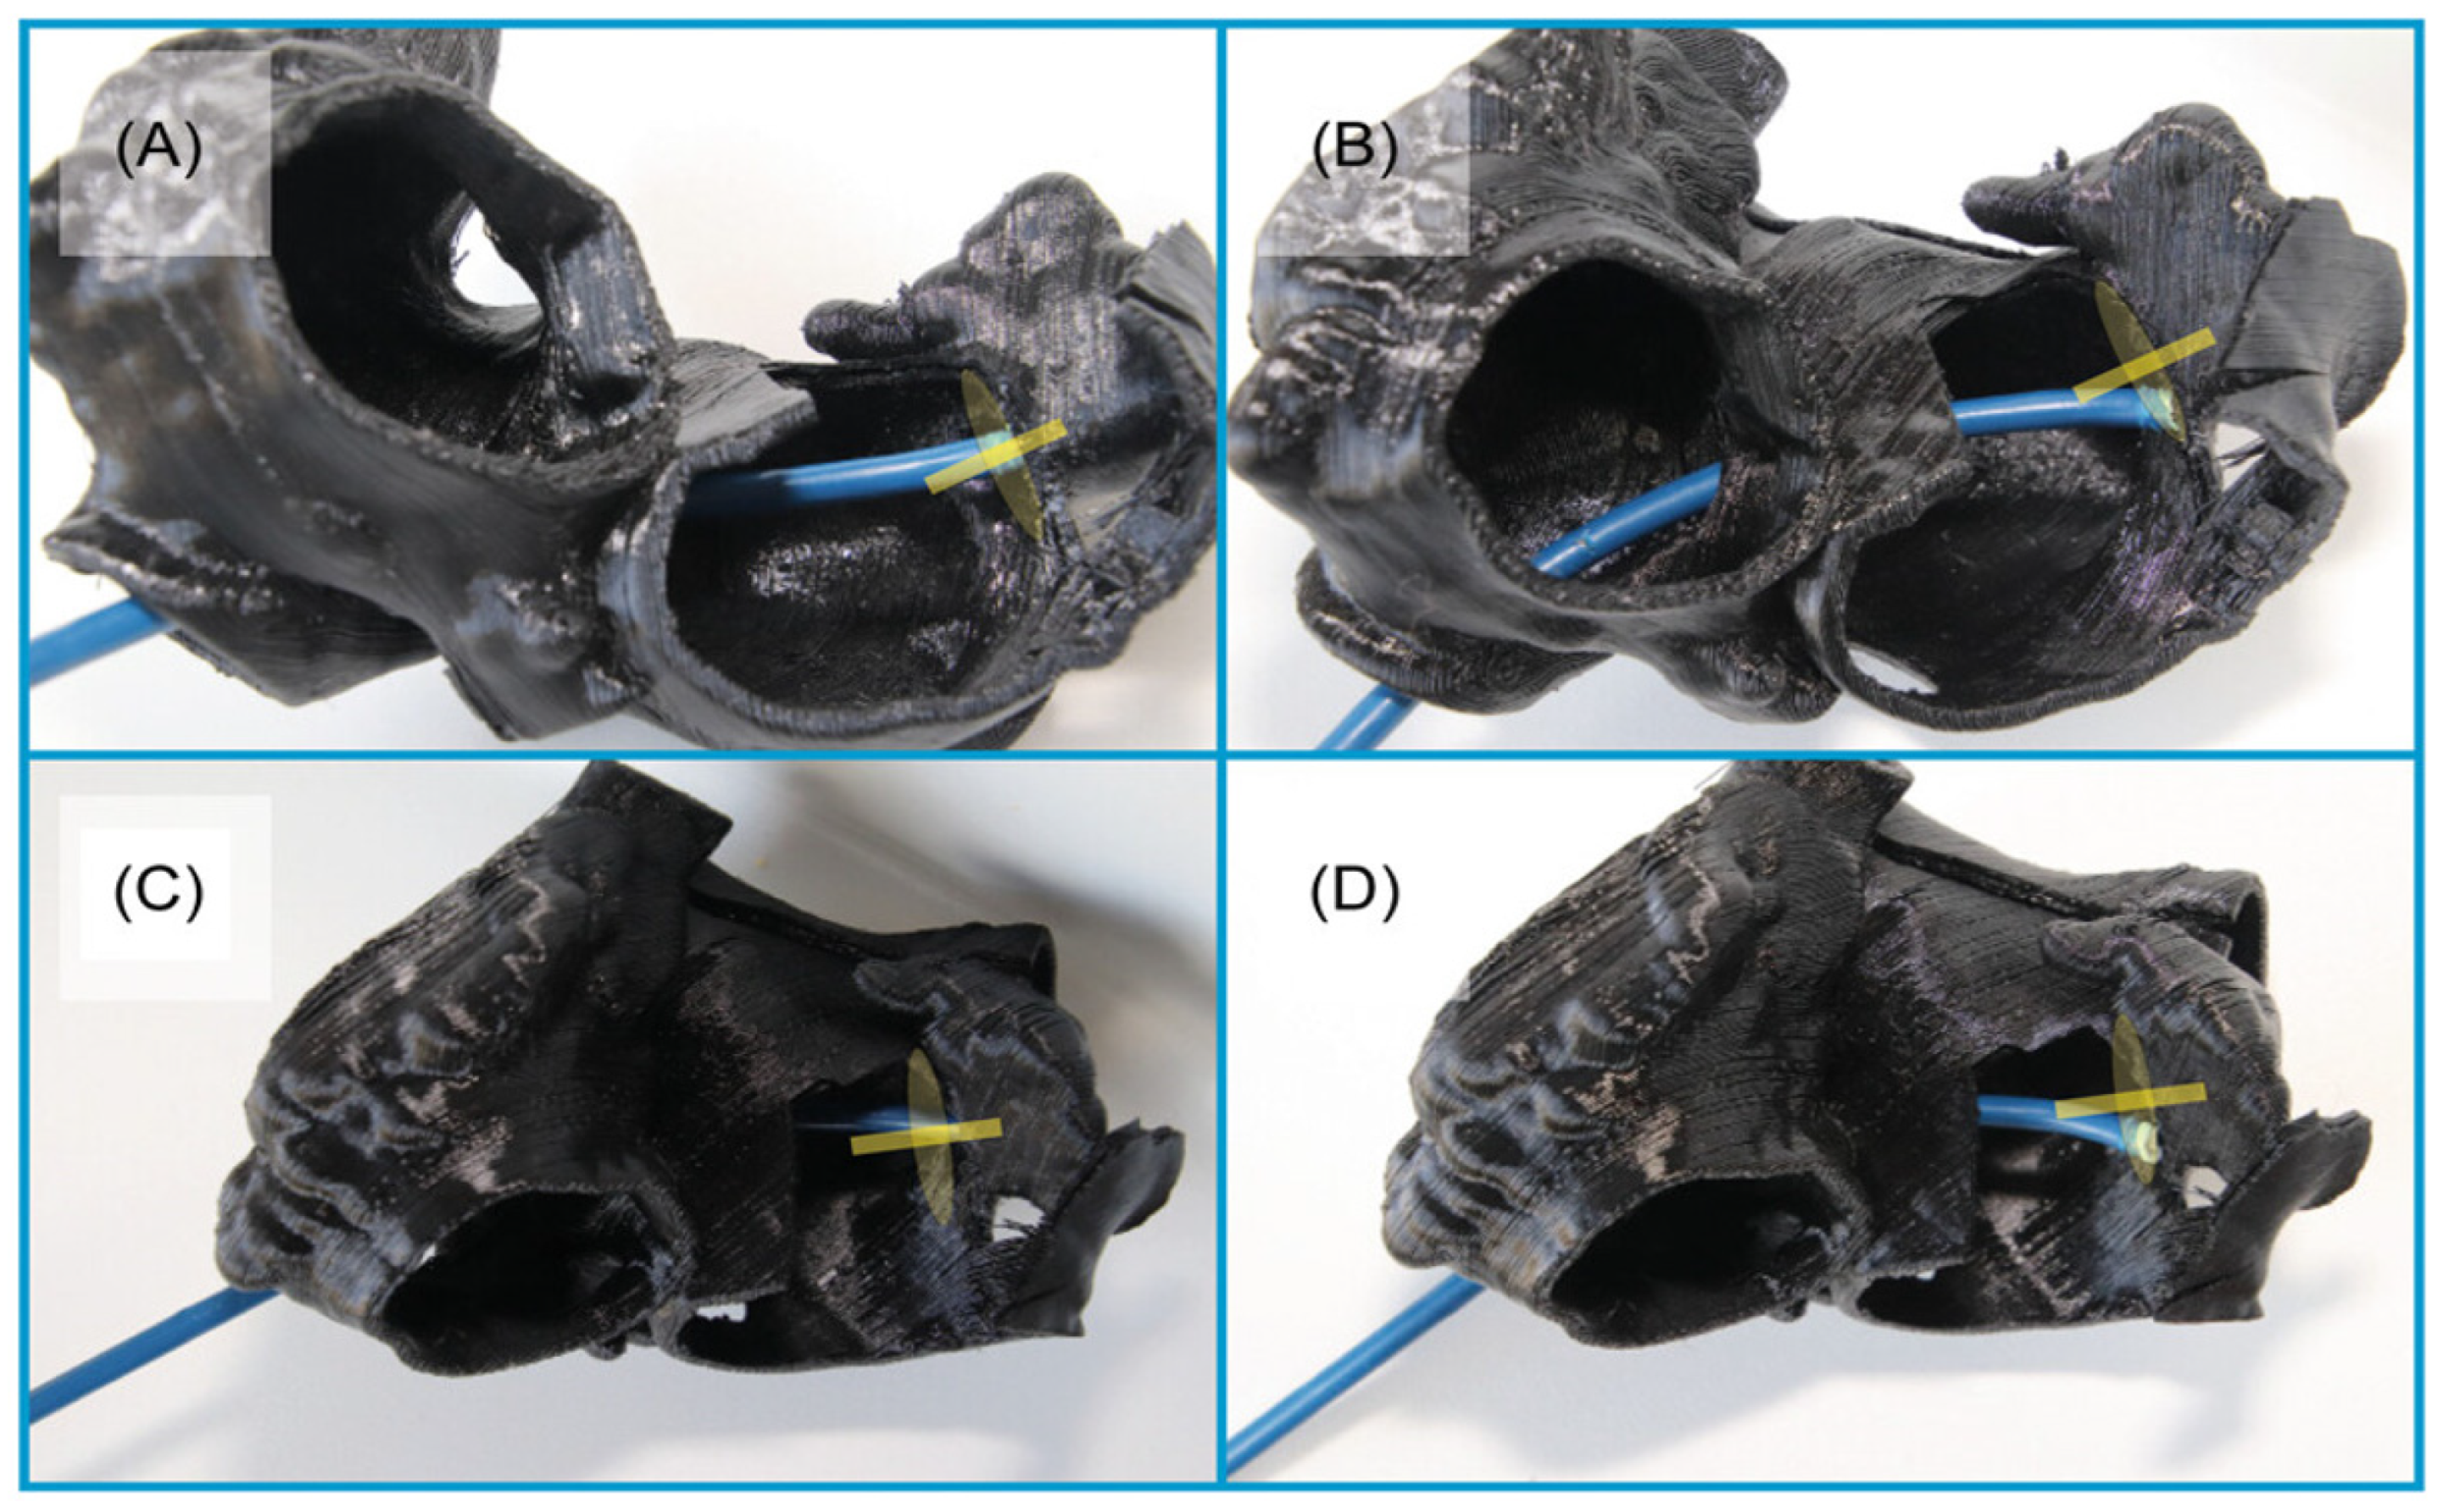

2.1.5. 3D Printing and Virtual Reality